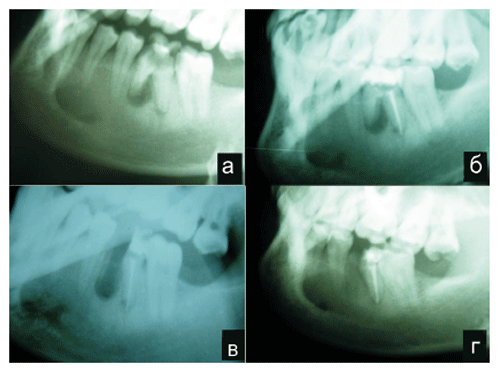

Для иллюстрации приводим следующий пример: Пациент Н., 29 лет, обратился в челюстнолицевое отделение РМЦ “Армения” 14 февраля 2004 г. с жалобами на боли в области правой половины нижней челюсти, которые иррадировали в ухо, висок, глаз и припухлость по проекции тела нижней челюсти. Себя считает больным уже третые сутки. Отмечает, что в начале болел 46 зуб, а через сутки появилась припухлость на правой половине лица. После клинико-рентгенологического исследования, установлен диагноз “Острый гнойный периостит нижней челюсти справа, обострение хронического гранулематозного периодонтита”. В тот же день после рентгенологического исследования, под местным обезболиванием провели вскрытие гнойного очага и дренирование раны. Была назначена антибактериальная и симптоматическая терапия, полоскание полости рта антисептиками. На боковой рентгенограмме нижней челюсти под мезиальным корнем 46 зуба видна кистогранулема размером 0,6 х 0,8 см (рис. 1).

После стихания острых воспалительных явлений на 10 сутки после вскрытия гнойного очага произведены пломбирование и гемисекция мезиального корня 46 зуба. После удаления мезиального корня с помощью острой ложечки удалена грануляционная ткань, проведены промывание полости антисептическими растворами и заполнение костного дефекта размельченным КМНП. Сверху лунка корня закры-валась тампоном смазанным мазью прополиса с об-лепихой, который менялся дважды (на 3 и 7 сутки). Произведено динамическое наблюдение через 1, 3, 6 мес.. Как видно на рентгенограмме, произведенной через 6 мес., лунка 46 зуба и околокорневой дефект не определяются. Видна органотипичная кость, которая по своей структуре практически не отличается от соседних участков.

Рис. 1. Пациент Н., 29 лет. Хронический гранулема-тозный периодонтит 46 зуба.

а) до пломбирования, б) после пломбирования, в) через 10 дней после гемисекции, г) через 6 мес. после гемисекции.